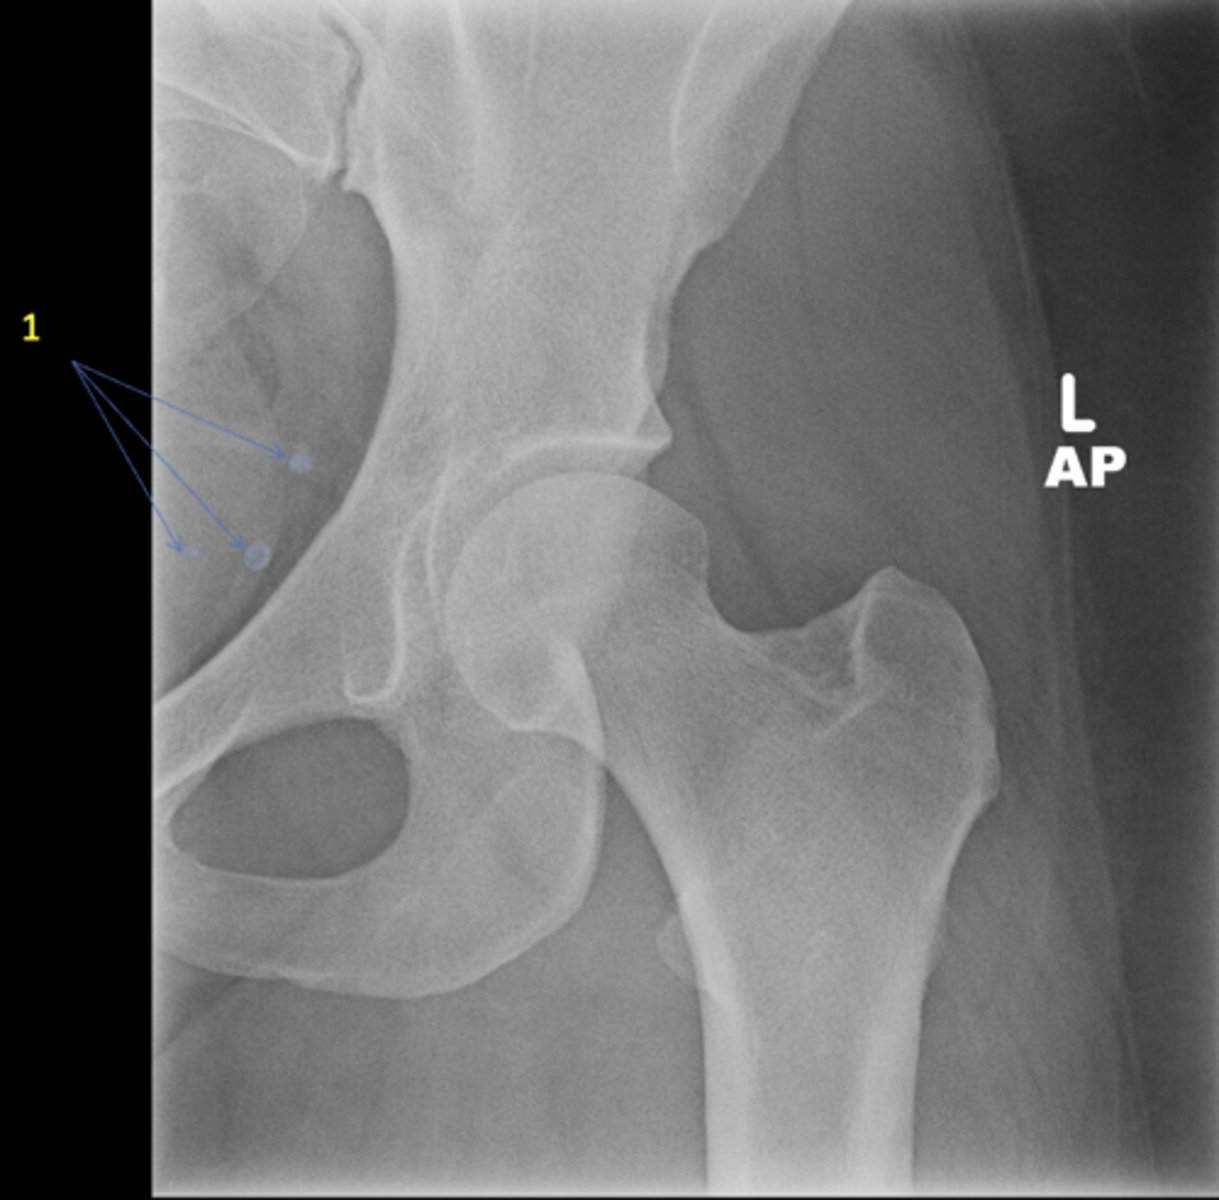

Left AP hip

View?

29

New cards

Phleboliths

ID 1

30

Obturator foramen

ID 2

31

Kohler's teardrop

ID 3

32

Gluteus medius

ID 4

33

Ischial tuberosity

ID 5

34

Acetabulum

ID 6

35

Anterior inferior iliac spine

ID 8

36

Lesser trochanter

37

Greater trochanter

ID 9

38

Sacroiliac joint

ID 10 (joint)

39

Sacrum

ID 11 (bone)

40

ID 12

41

Anterior superior iliac spine

ID 13